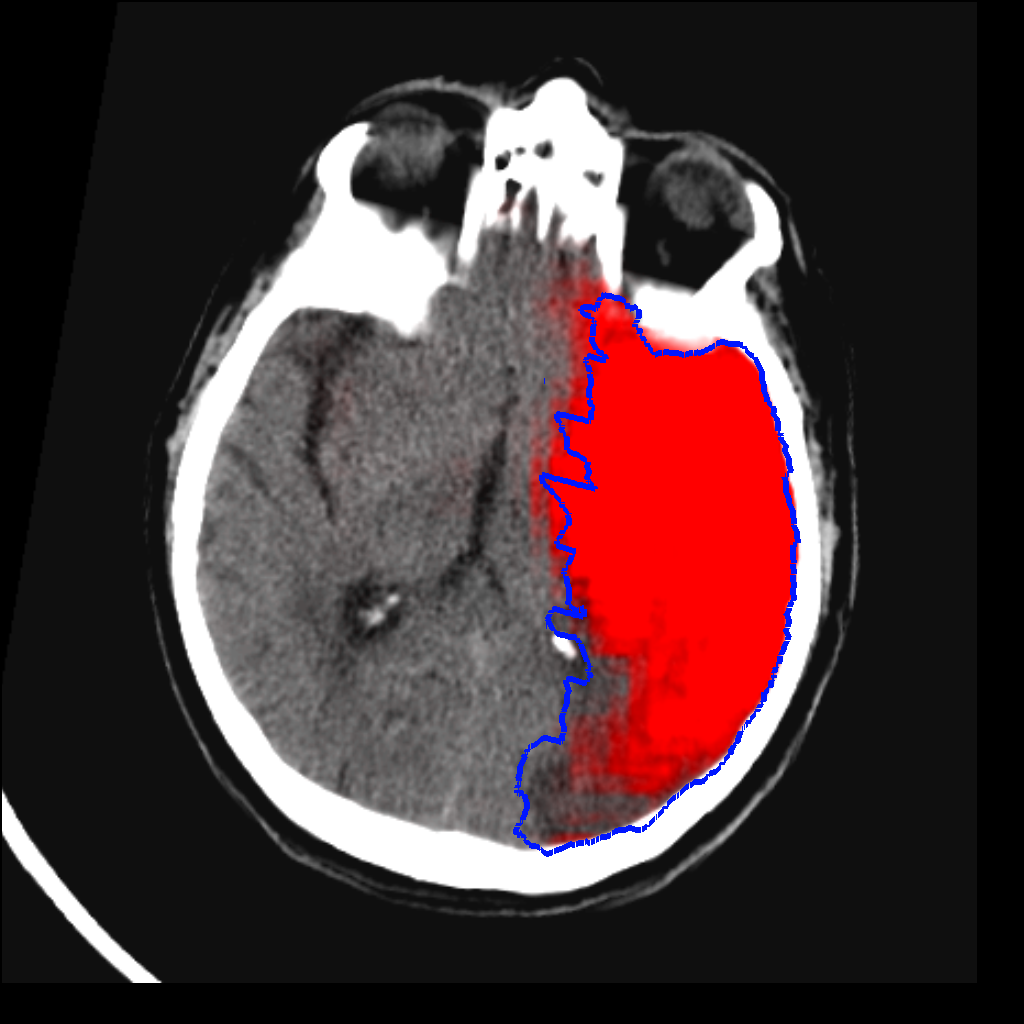

Fig. 3 shows a scatter plot and a Bland-Altman plot of the true and predicted volumes for all subjects in the testing folds using the proposed method. The mean volume error is -2.8 ml (the prediction is a slight underestimation) and the mean absolute volume error is 36.7 ml. The mean Dice score is 0.48. A representative set of predictions is shown in Fig. 4.